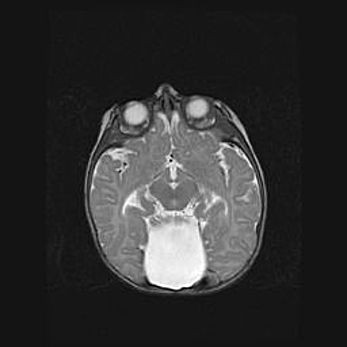

Аномалия Денди-Уокера. Признаки гипоплазии мозолистого тела.

Возраст: 5 месяцев 3 дня

Вес: 5550 г

Пол: мужской

Окружность головы: 39 см

Срок гестации: 40 недель

Аномалия Денди-Уокера – это порок развития головного мозга, для которого характерна триада симптомов: гипотрофия или аплазия червя мозжечка и/или полушарий мозжечка, расширение четвёртого желудочка с формированием ликворной кисты задней черепной ямки, гипертензионная гидроцефалия различной степени.

Гипоплазия мозолистого тела относится к дефектам внутриутробного этапа развития мозговой ткани, возникающим в процессе закладки структур головного мозга, что происходит на начальных этапах развития эмбриона.